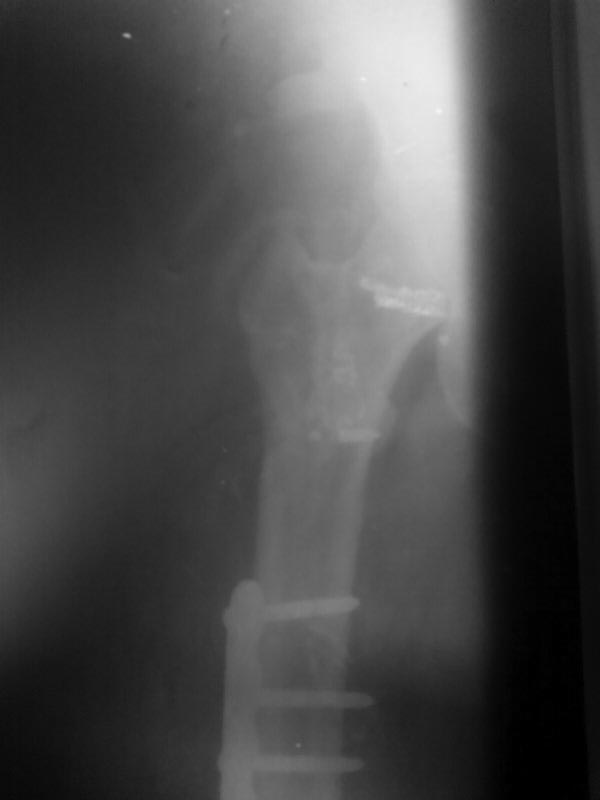

Так выглядит проксимальный отдел бедра на данный момент.

|